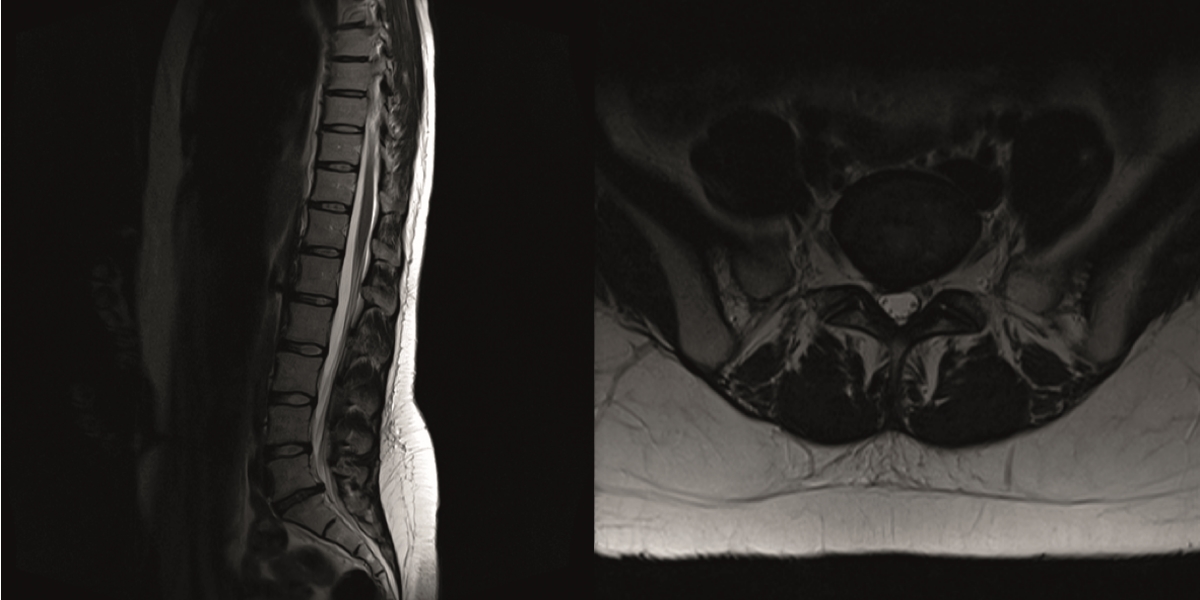

The preoperative standing image of the lumbar spine revealed a flat back with no obvious degeneration of the adjacent segment L1/L2 (Fig 6ab). The implants seemed regularly placed. After wide laminectomy, the spinal canal was open over the whole lumbar spine, illustrated on the MRI scan (Fig 6c).

The sagittal and axial T2-weighted MRI showed grade III disc degeneration with diffuse right-sided disc bulging (Fig 12).